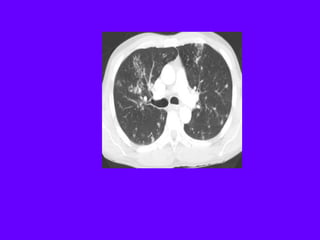

Centrilobular emphysema due to smoking. The periphery of

the lung is spared (blue arrows). Centrilobular artery (yellow

arrows) is seen in the center of the hypodense area.